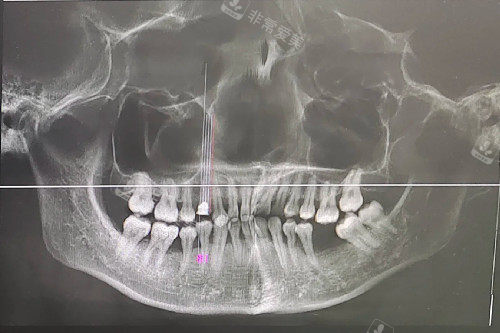

下面为大家详细介绍昆明医科大附属口腔医院牙齿矫正、种植牙、根管治疗、拔牙等项目的收费情况。

一、牙齿矫正价格

牙齿矫正主要用于改善牙齿排列不齐、咬合不良等问题。

昆明医科大附属口腔医院的牙齿矫正价格因矫正方式而异。

二、种植牙价格

种植牙是目前修复缺失牙齿比较理想的方式。

该医院种植牙的价格受种植体品牌、牙冠材料等因素影响。

三、根管治疗价格

根管治疗主要用于治疗牙髓炎、根尖周炎等牙髓疾病。

根管治疗的收费与牙齿的根管数量有关。

四、拔牙价格

拔牙的收费取决于牙齿的生长位置和拔除难度。